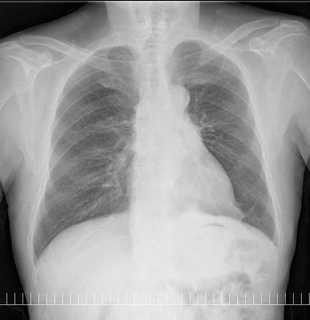

こちらを見て下さい。

わかりにくいかもしれませんが、このあたり。

気管が追いにくい、無くなっているようにも見えます。